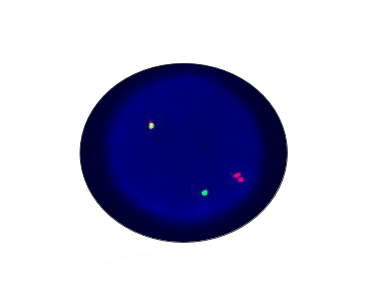

MLL Breakapart

Probe Description: MLL

Cat.No.: CF1262